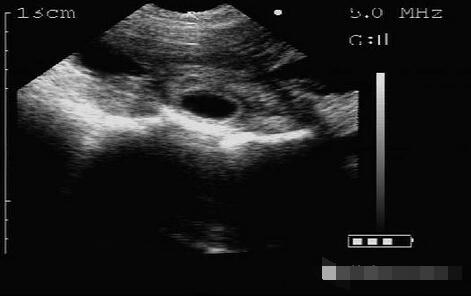

21天检测怀孕图(1/7)